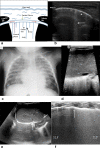

Cross-sectional imaging modalities like MRI and CT provide images of the chest which are easily understood by clinicians. However, these modalities may not always be available and are expensive. Lung ultrasonography (US) has therefore become an important tool in the hands of clinicians as an extension of the clinical exam, which has been underutilized by the radiologists. Reinforcement of the ALARA principle along with the dictum of "Image gently" have resulted in increased use of modalities which do not require radiation. Hence, ultrasound, which was earlier being used mainly to confirm the presence of pleural effusion as well as evaluate it and differentiate solid from cystic masses, is now being used to evaluate the lung as well. This review highlights the utility of ultrasound of the paediatric chest. It also describes the normal and abnormal appearances of the paediatric lung on ultrasound as well as the advantages and limitations of this modality.